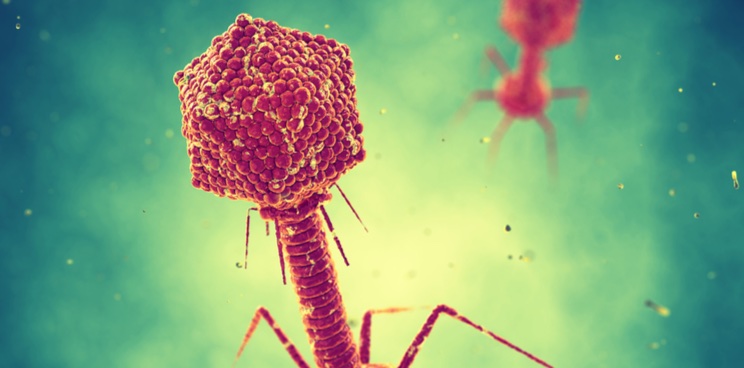

Do Phages Hold the Key to Modulating the Microbiome?

The human microbiome is emerging as a target for treating a wide range of diseases, but it’s still a young field and there are lots of unknowns. Philip discussed with the CEO of BiomX whether phages may be the key to targeting specific bacterial strains in the microbiome. In the last decade, scientists have found […]